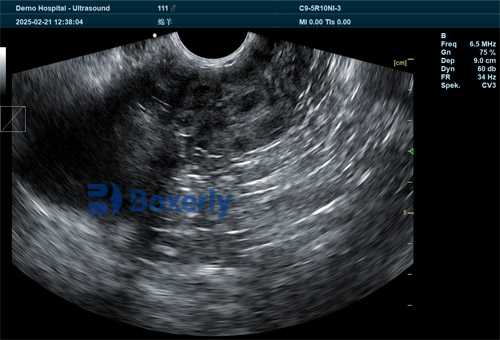

With the help of a modern sheep ultrasound machine, particularly portable B-mode devices, veterinarians and farmers can now obtain real-time visual insights into the ewe’s reproductive tract. This includes the presence of a corpus luteum, follicle development, early pregnancy diagnosis, fetal viability, number of fetuses, and any abnormal uterine content.

A machine with at least 256 levels of grayscale and an HD screen provides the clarity needed to differentiate between a fetus and other structures. Real-time feedback is essential for identifying heartbeat and fetal movement.

Probe Type

Linear rectal probes are ideal for transrectal scanning in early gestation, while convex probes offer wider viewing fields and are commonly used during mid to late pregnancy stages.